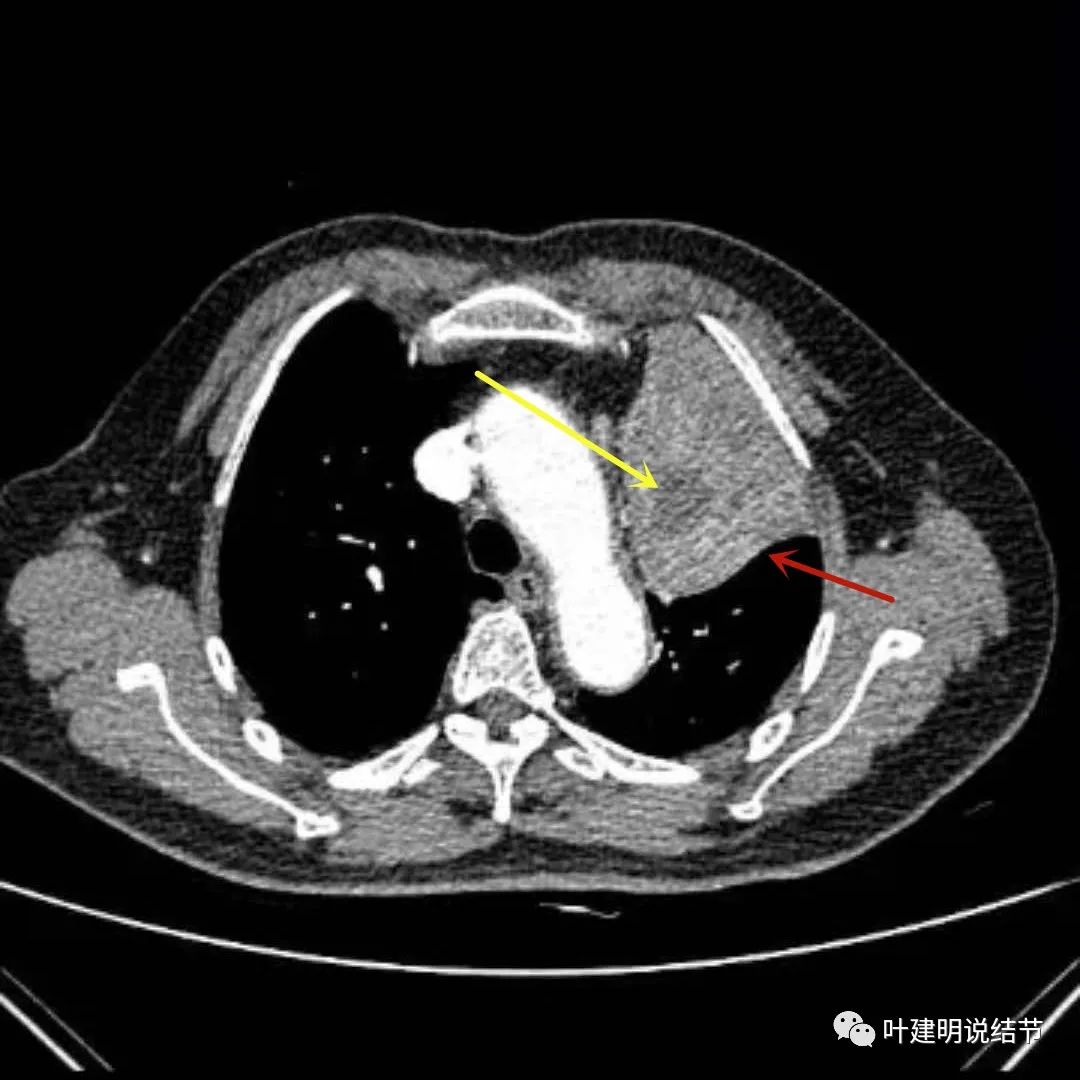

上图绿色箭头所指区域考虑不张的肺组织,红色箭头所指附近为肿瘤,且有膨胀性